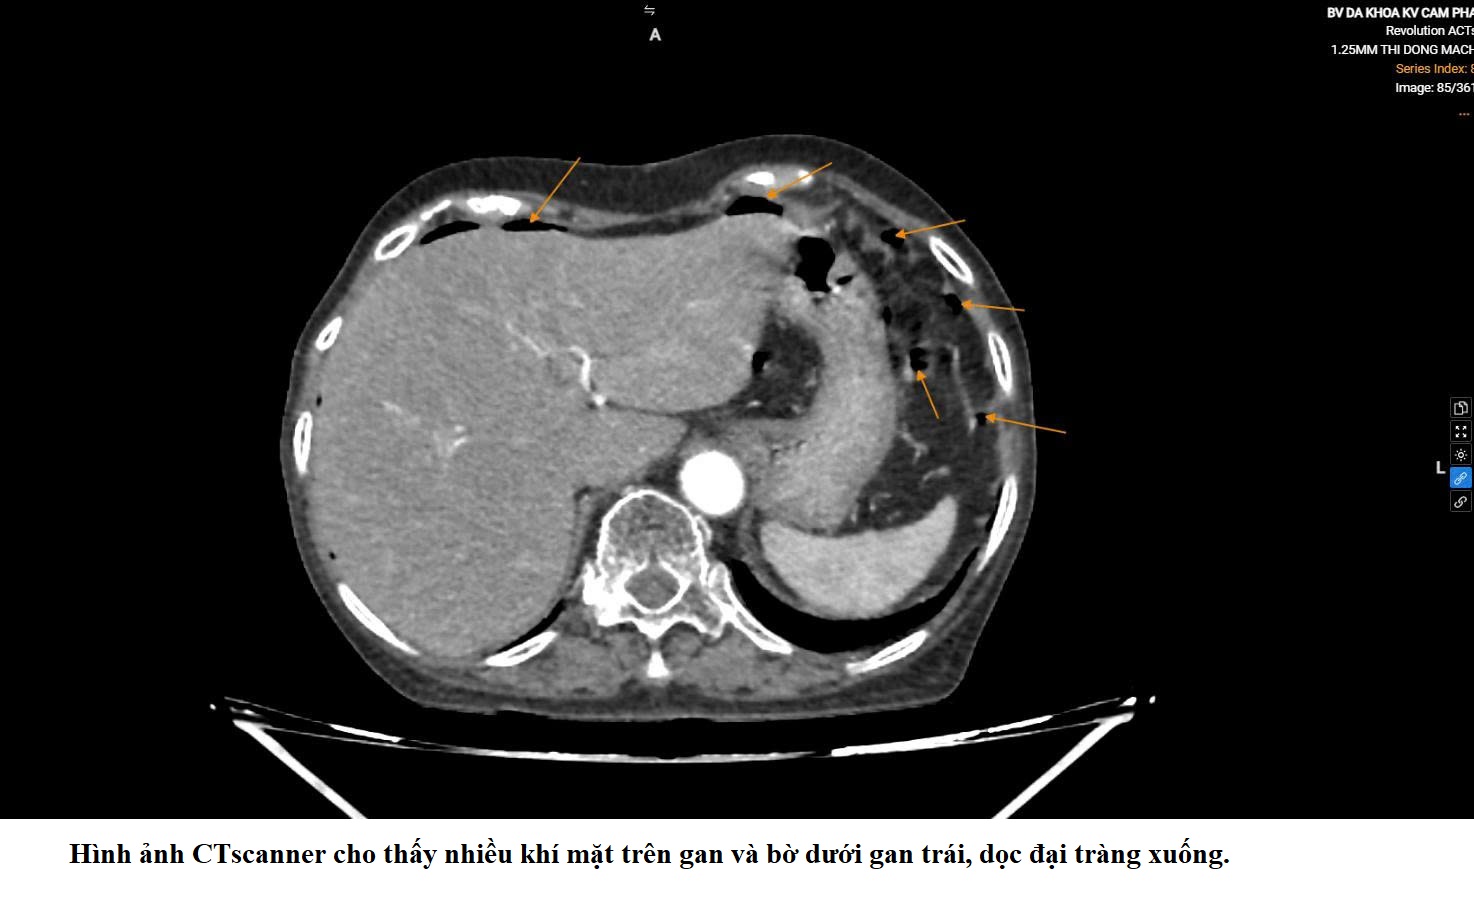

Qua thăm khám và các xét nghiệm cận lâm sàng, các bác sĩ xác định bệnh nhân bị viêm phúc mạc do thủng đại tràng trái và nhanh chóng chỉ định phẫu thuật nội soi cấp cứu. Ê-kíp phẫu thuật gồm BS.CKI.Phan Văn Đức, BS.Vũ Thái Bảo, BS.CKI.Phạm Ngọc Hải (Khoa Ngoại), BS.CKI.Hoàng Thị Ngát (gây mê) đã tiến hành cắt đoạn đại tràng chứa lỗ thủng, dẫn lưu ổ bụng và làm hậu môn nhân tạo. Nhờ được can thiệp kịp thời, tình trạng nhiễm trùng được kiểm soát, người bệnh qua cơn nguy kịch và hiện đang tiếp tục hồi phục.